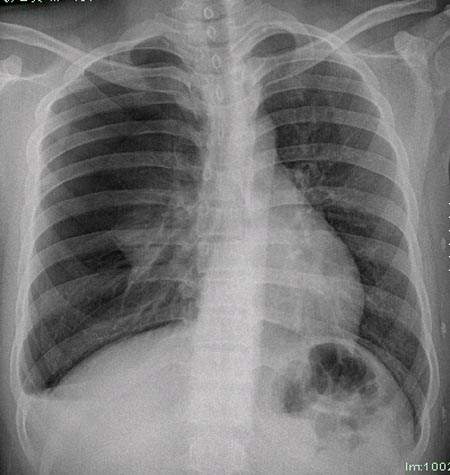

m21y既往体健,否认结核、支扩等病史;1周前患上感,无明显咳嗽,自觉无明显不适。单位体检透视时发现右侧液气胸!cr及ct如下(肺组织窗:l:-598hu w:1132hu):请大家会诊!!

右侧巨大含气囊性病变,壁薄、光整、其外侧见气体。右肺压迫性肺不张、胸腔内见少量积液。纵隔向左侧移位。左肺未见异常。诊断:1.右侧含气肺囊肿(先天性)。2.右侧液气胸。(少量液体)3.右肺压迫性肺不张。我也遇见一例这样的病人。女性。股骨外伤就诊。常规胸片发现右侧囊性病变。